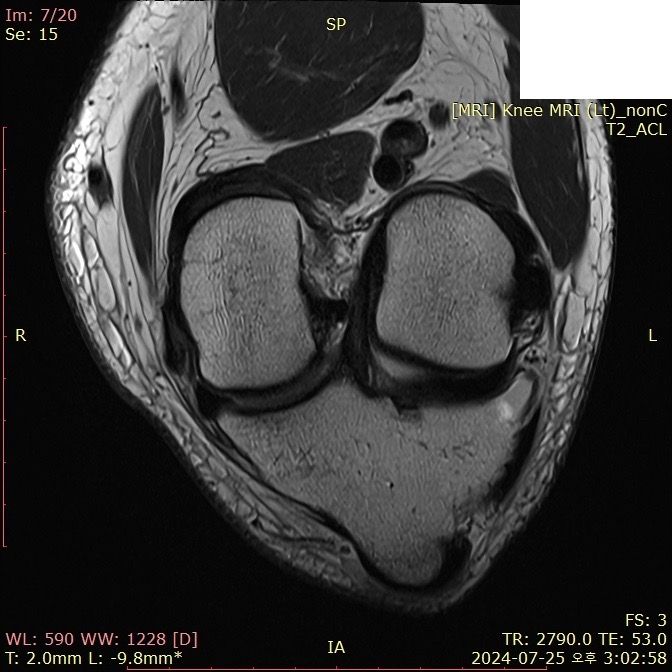

무릎 ACL(전방십자인대) 확인 부탁드려요

아스팔트에 무릎을 부딪쳐 심하게 부어서 mri 찍어봤는데 슬개골 비변위성 골절 판독 받은 건 기억 나는데, 인대는 기억이 잘 안나서 여쭤 봅니다..

전방십자인대 괜찮은가요...??ㅠㅠ

• 1번 째 사진